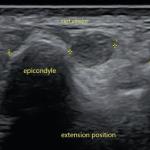

Hygroma dans un contexte d’amputation bilatérale des membres inférieurs

Une enfant de 11 ans est amputée des membres inférieurs à la suite d’un choc toxique survenu dans le contexte d’une...